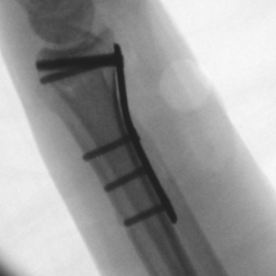

Röntgenbilder